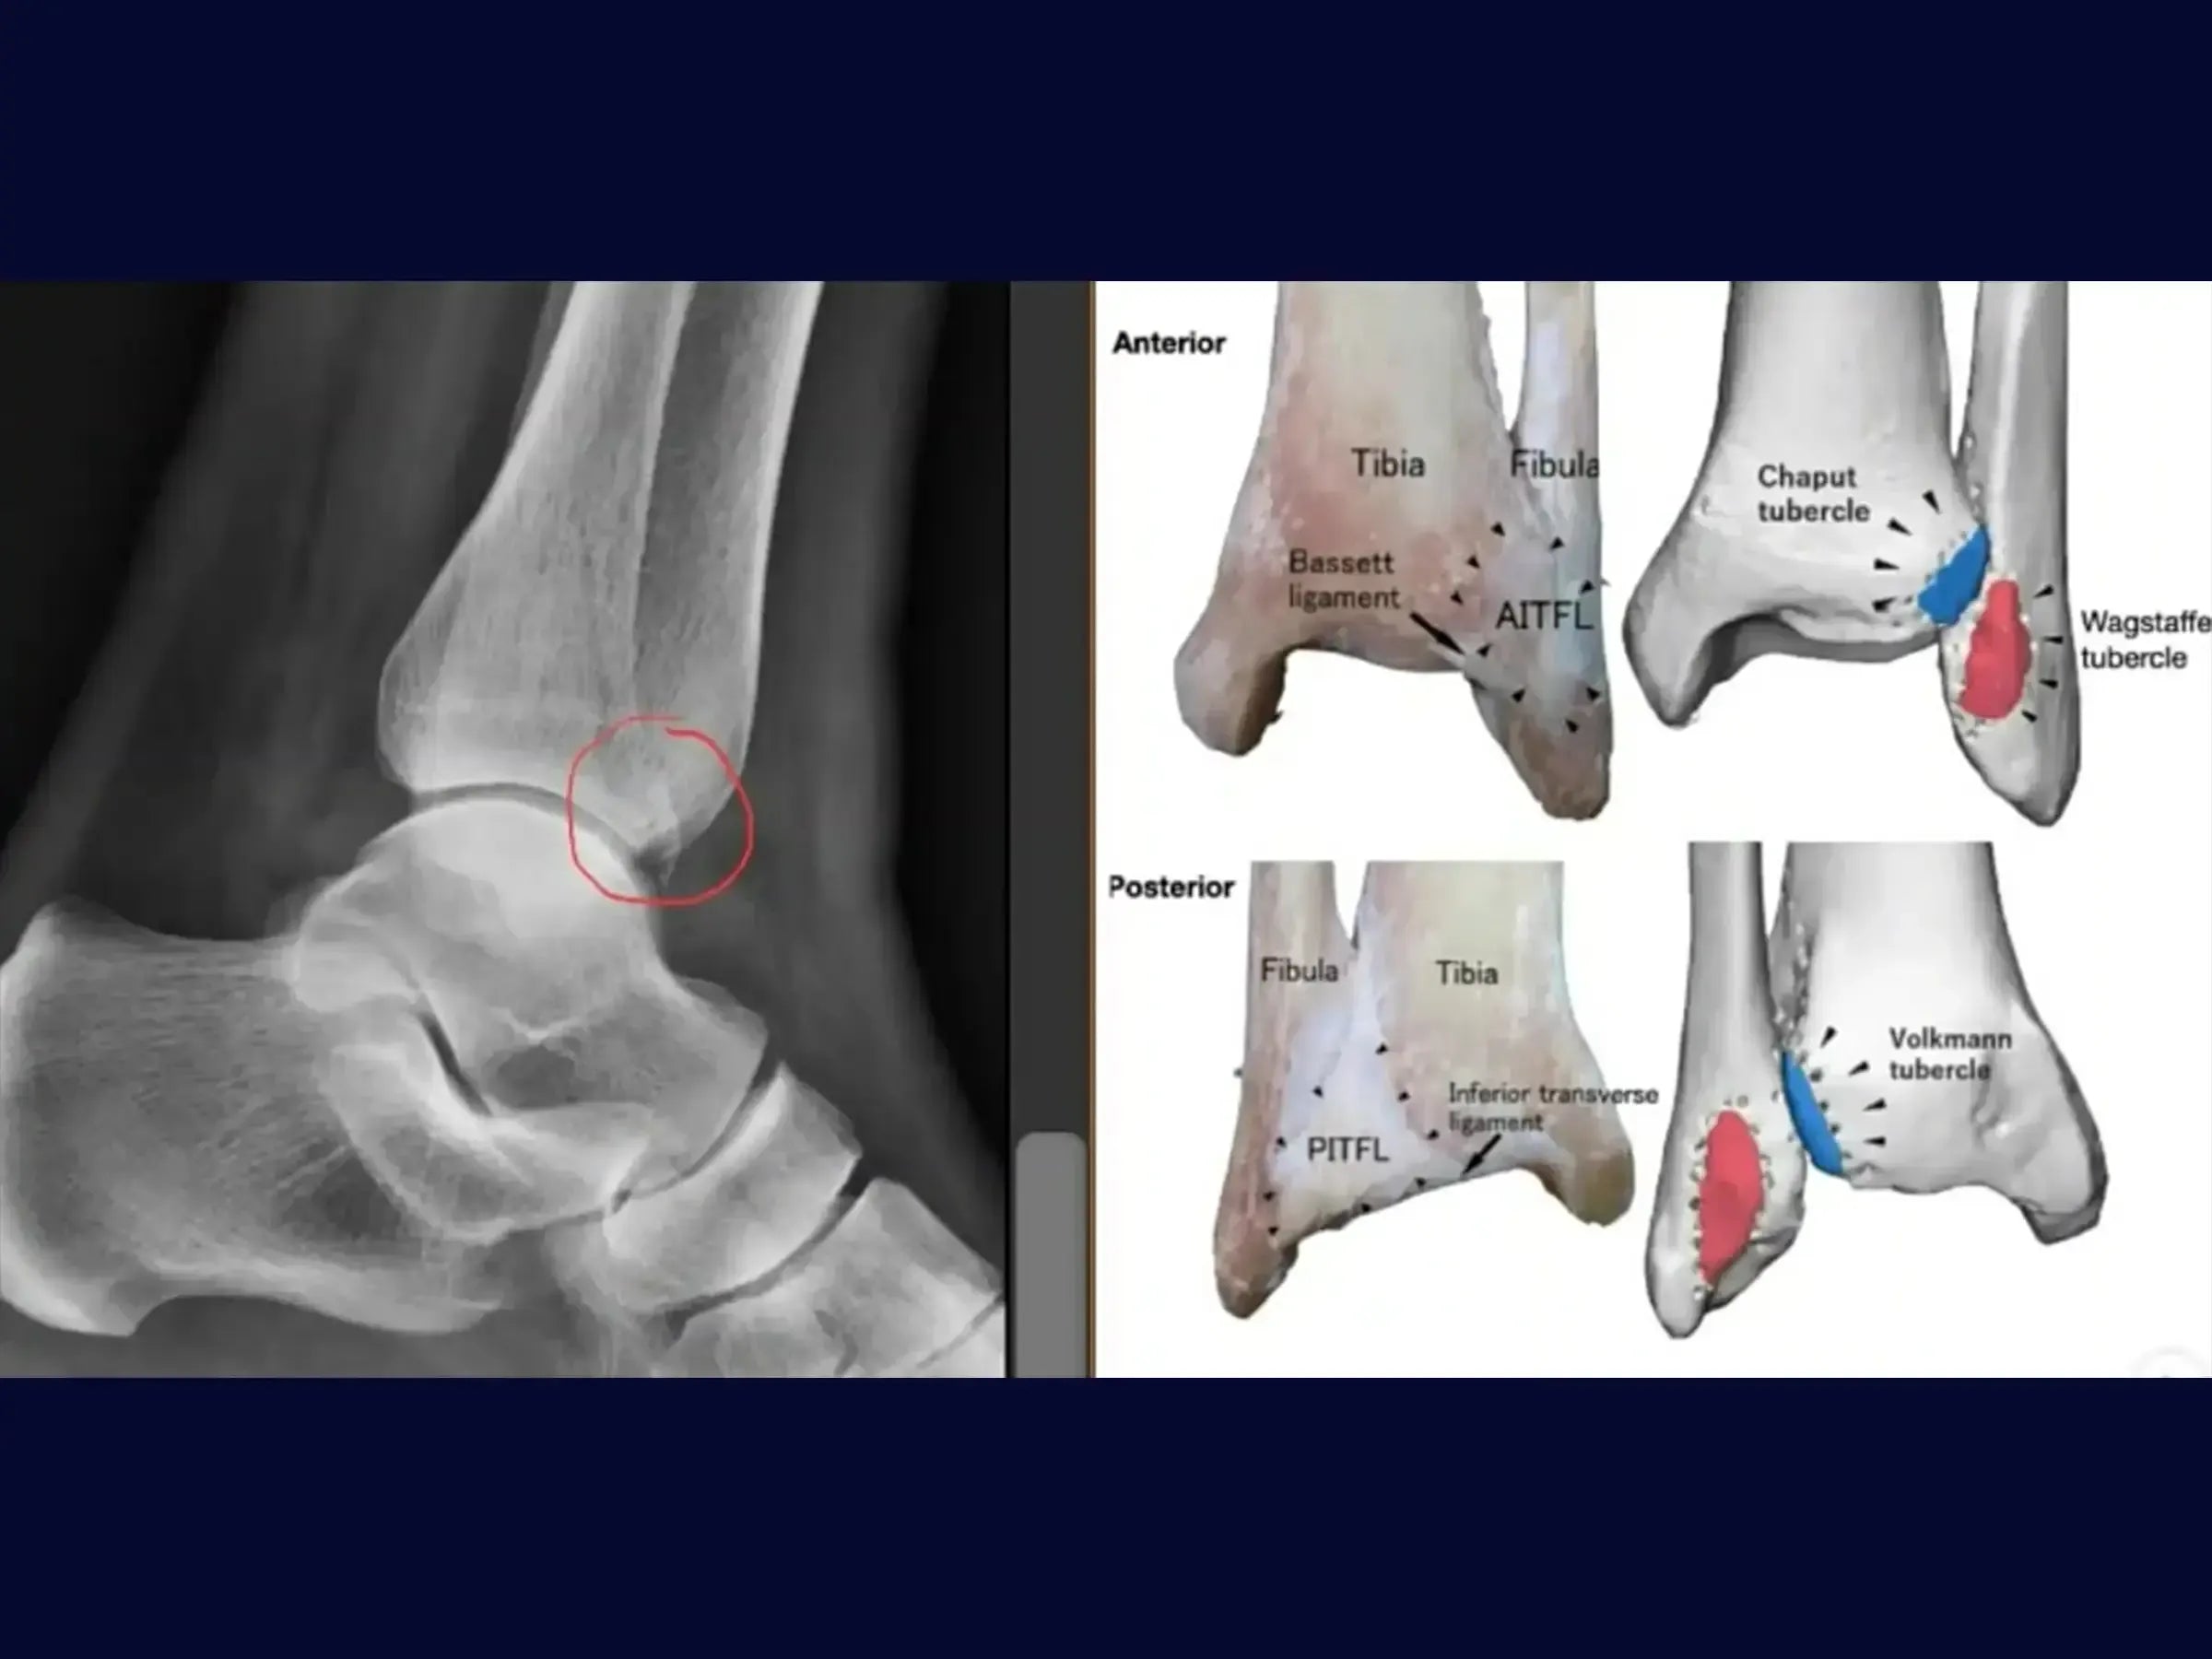

- Diagnóstico Preciso: Metodologia para identificar o fragmento de Wagstaffe em radiografias, reconhecendo seu significado na instabilidade sindesmótica.

- Identificação e manejo do fragmento de Wagstaffe em fraturas do maléolo lateral.